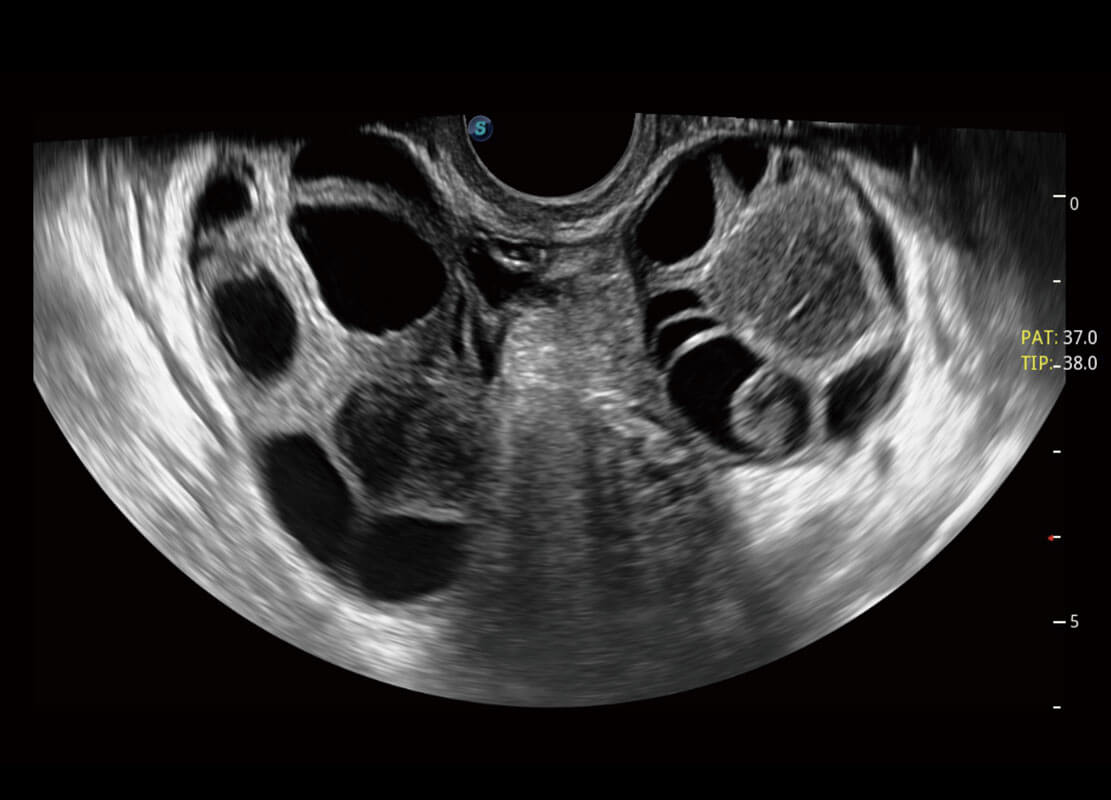

生殖健康

P60优异的图像质量搭载专科探头,在妇科基础疾病的诊断、卵泡生长的监测、输卵管通畅情况的判别等方面为您提供生殖应用方案。

• 腔内妇科-宫腔分离

• 腔内妇科-卵巢